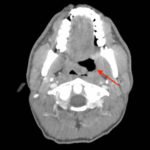

The photograph demonstrates an area of ulcerative tissue at the left palatine tonsil without surrounding erythema or purulent drainage. The computed tomography (CT) scan shows a large ulceration of the left soft palate and palatine tonsil (red arrow). There is no evidence of skull base osteomyelitis. There is suppurative lymphadenopathy with partial left jugular vein compression due to mass effect (yellow highlight). There is mild nasopharyngeal airway narrowing with architectural distortion (blue arrow), but no other evidence of airway obstruction.